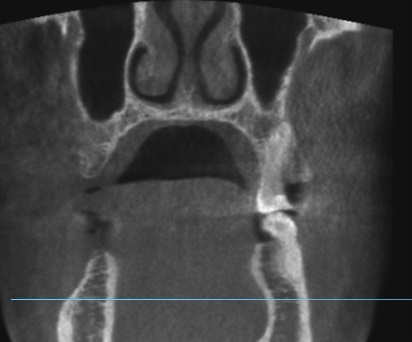

Пропила 2 курса антибиотиков. Хирург сказал, что все зубы в порядке, и отправил домой нервы лечить. Рентгенолог увидела повреждения и сказала не есть больной стороной и вообще не жевать. Это избавило меня от постоянной боли. Но стоит только дотронуться до семёрки, появляется неприятное очущение, как будто он висит на волоске. И в месте удалённой 5 зуд. Как будто кость сломана. Фото с 3д рентгена во время курса антибиотиков.

По этому снимку можно сказать, что немного повреждена передняя стенка, но это не является проблемой. К хирургу обратиться стоит, для того чтобы оценить процесс заживления.